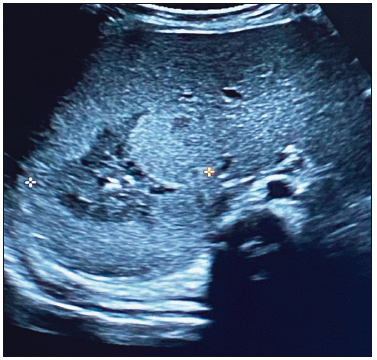

Al ingreso presentó hipotonía axial sin dismorfias. Se solicitó una ecografía abdominal en la que se visualizó una imagen ecogénica hepática (segmento VI - VII), con bordes difusos, de 4 x 3.5 x 3.1 cm, que coincidió bioquímicamente con el aumento de las enzimas hepáticas y leve anemia. La AFP estaba dentro de valores normales para la edad (42,334 ng/ml), con plaquetas normales. (Figuras 1 A B C).

Figura 1. C